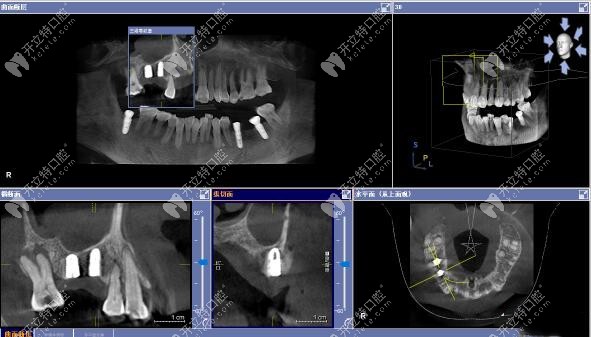

3D數(shù)字化導(dǎo)板上頜竇區(qū)種植案例

▲術(shù)后CT顯示:上頜15號(hào)、16號(hào)缺牙位置的植體,均已達(dá)到了預(yù)期位置。